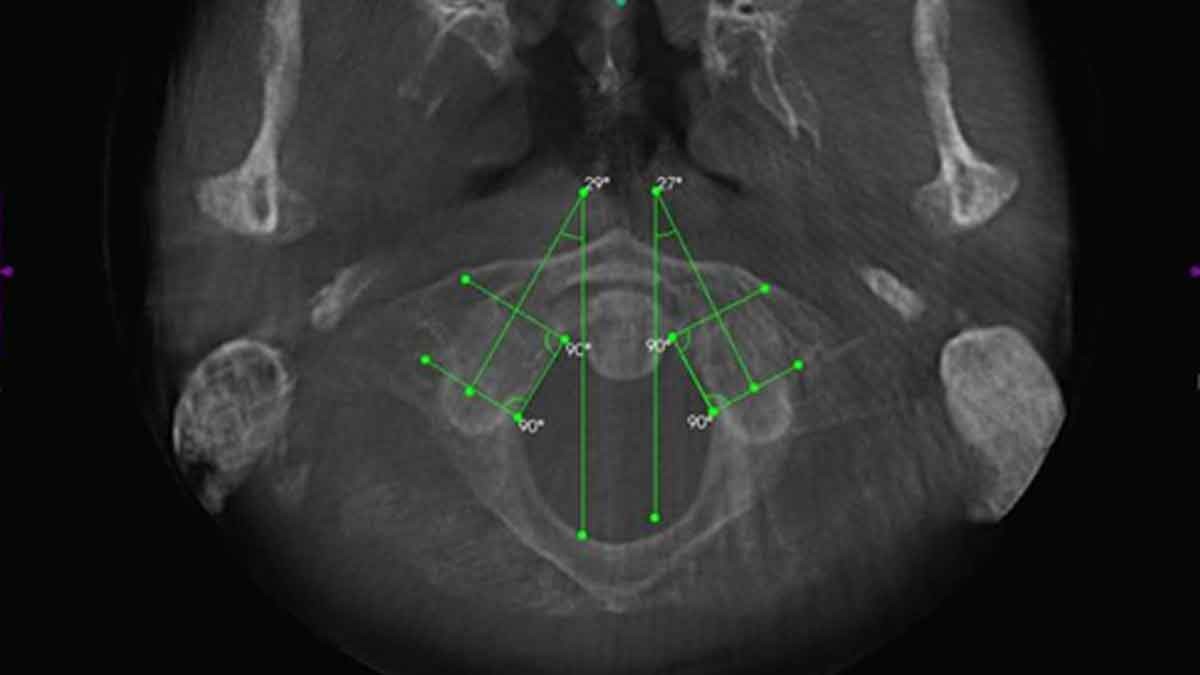

AXIAL VIEW OF FORAMEN MAGNUM AND ATLAS

This view allows the doctor to study the alignment of the upper cervical spine in a traditional APOM view. In chiropractic, the APOM is viewed from the posterior to the anterior to keep left and right right.